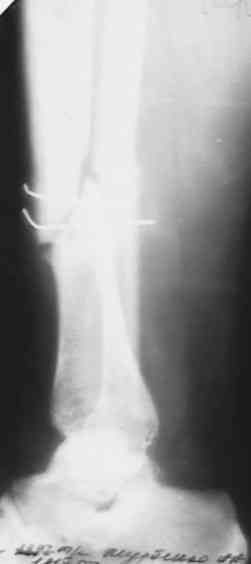

поступил больной с замедленной консолидацией перелома голени . Травма ДТП 15 мая 2007года (6 мес. Назад) . Первичный диагноз : открытый перелом голени 2 А степени (Каплан-Маркова) . В одной из районных больниц выполнена трансфиксация , я так понимаю , по Паппу спицами и наложена гипсовая повязка . .Затем больной находился под наблюдением травматолога поликлиники , Свищей , длительно незаживающих ран , вроде (со слов больного) не было . ВТЭК, 2 группа . Но больной хочет ходить , (вроде нормальное желание ) На сегодняшний день имеем вот такую картинку (см. . Снимки) Анализы абсолютно нормальные . Температура 36,6 в течении суток . Клинически : отёк голени , движения в КС и голеностопном суставе практически в полном объёме . В зоне перелома определяется безболезненная подвижность , опора на конечность невозможна . PLS !!!подскажите , тактику лечения!Мой план : АВФ (БИОС недоступен) .Предполагаемый план операции: Проксимально стержень , дистально спица во фронтальной плоскости с учётом смещения . Парафрактурно оставляю <пустые> кольца . Открываю зону перелома и удаляю спицы . Остеотомия малоберцевой кости . Дистракция . В ране иссекаю межотломковую рубцовую ткань . Вскрываю костномозговые каналы . Восстановление длины и оси . Если получится ,то одномоментно . Если не нарвусь на гнойный очаг в области перелома , выполняю декортикацию . Возможно с применением аутотрансплантанта из крыла. Провожу репонирующие спицы ,стабилизирую АВФ . При наличии гнойного очага - то же самое + дебридмент , но без костной пластики и декортикации . Затем ,при благоприятном течении раневого процесса , ранняя нагрузка . При наличии проблем - ограничение нагрузки до санации раны , <аккордеонная техника> (по Голяховскому) . Прошу , выскажите замечания по технике и тактике лечения .С уважением Д.Б.

Мы бы убрали спицы через проколы кожи, по возможности. Затем аппаратом бы дозированно восстановили длину и ось. После этого закрыто

заштифтовали. Там по виду тугой ложный сустав, на дистракцию они обычно хорошо откликаются регенератом.

сегодня поставил аппарат , проблем не было . спицы убрал , но пришлось рубить малоберцевую из маленького разреза . Постепенно восстановлю длину и ось . как получится покажу снимки .Спасибо огромное всем коллегам ,откликнувшимся на вопрос !